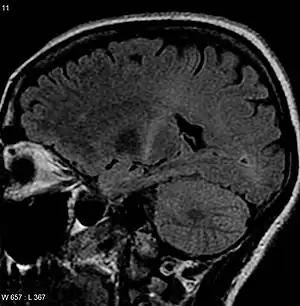

![]() | |

| An MRI with increased signal in the posterior part of the internal capsule that can be tracked to the motor cortex, consistent with the diagnosis of ALS | |